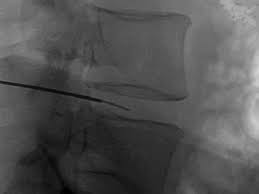

Πλάγια ακτινοσκοπική προβολή του ανωτέρου περιστατικού. Ο έλεγχος σε 2 επίπεδα εξασφαλίζει με βεβαιότητα την ευστοχία της τεχνικής.